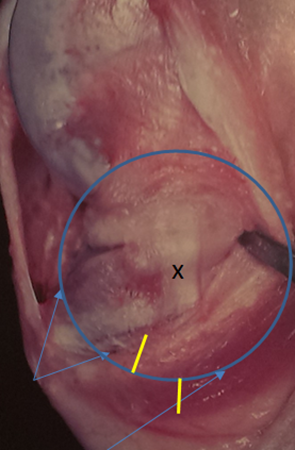

Indications